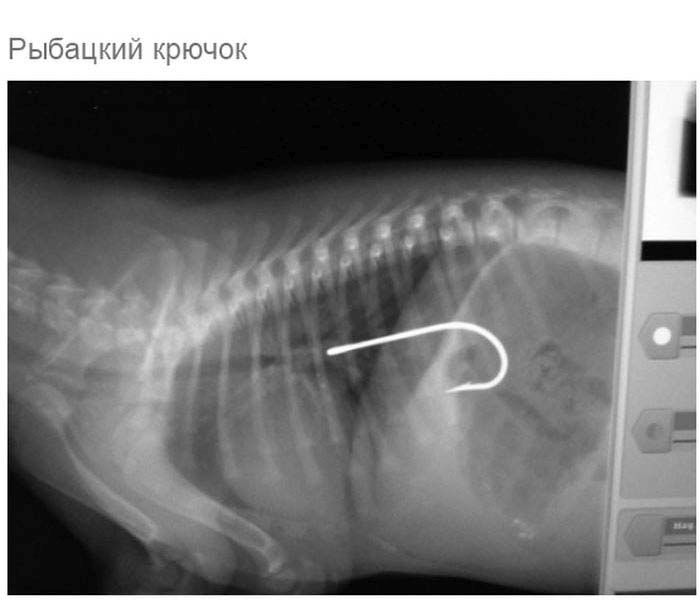

» Что может оказаться в желудке собаки

Что может оказаться в желудке собаки